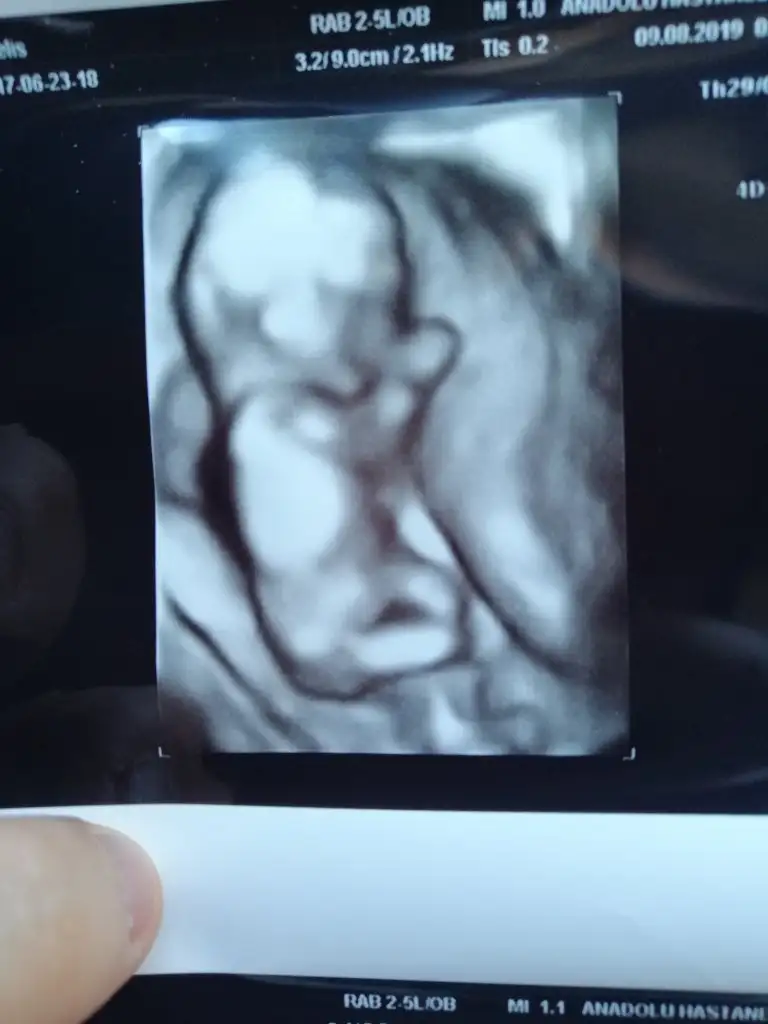

11+6 haftalik

Bizde 11+5 olduk. Bizim bu görüntüyüde bakarmısınız

Arada kaldım ama kız gibi geldi bana Canım doktorun tahmin de bulundu muArkadaşlar yorum yapabilir misiniz 14 haftalık 2 boyutlu vermedi